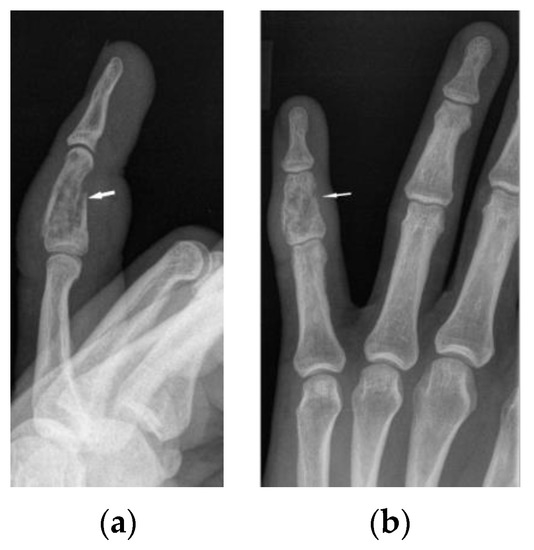

The radiographic appearance of phalanges occupied by sarcoidosis includes lytic lesions of various sizes, called cysts. Cystic lesions, mostly punched-out, may be accompanied by soft tissue nodules. The presence of large cysts increase the risk of pathological bone fracture [20] (Figure 6a,b). Numerous small cysts are more frequently observed. The articular surfaces are preserved, although cysts located in the subchondral layer might mimic erosions (Figure 7). Periosteitis is uncommon.

Features of bony destruction may be permeative and cause scalloping of the cortex, whereby cortical margins are preserved. Bone destruction with moth-eaten pattern may involve the cortex, usually with associated soft tissue swelling [19]. The cortical and trabecular architecture is usually remodeled [20]. The phalanges of the second and third fingers of the hand are most often involved, leading to the image of sausage-shaped fingers [20].

Figure 1. X-ray of the finger. Sarcoidosis. Cystic lesions in the middle phalanx head (white arrow).

Figure 6. X-ray of the left hand, lateral view (a), PA (b). Osteolytic pattern in the middle phalanx with pathological fracture (white arrows). Soft tissue swelling.